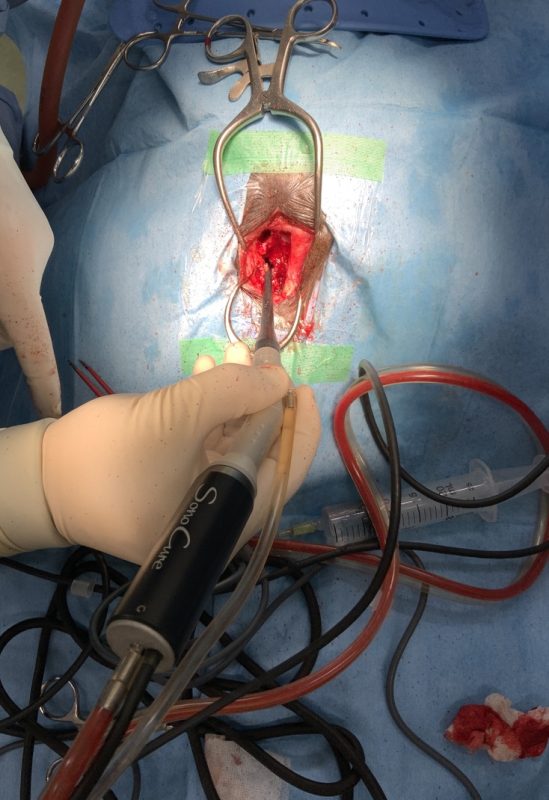

再手術

2025年12月14日(日)

CT検査の結果がいつもお世話になっている病院へ届いて、院長先生から明日か明後日でも手術できると連絡があった。急だが年末もあるので、今日病院に連れて行って明日土曜日に手術してもらうことにした。

2025年12月15日(土)

手術は15時すぎから1時間半ほどでおわったようです。